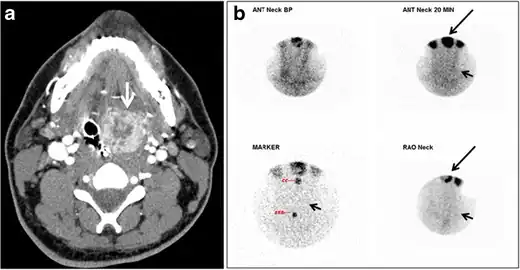

Fig. 18. Lingular thyroid in a 33-year-old male who presented with oropharyngeal bleeding. an Axial enhanced neck CT scan at the level of mandible demonstrates a 3 × 3 × 3.4 cm round, partly well-delineated, heterogeneously enhancing lesion (white arrow). It is predominantly on the left side of the oropharynx and to some extent at the mid part of the base of the tongue. The thyroid gland was normal (not shown). b Image of the anterior face and neck taken 20 minutes after Tc99m-Pertechnetate injection shows absent thyroid radiotracer uptake in normal thyroid anatomical location (black short arrows). There is an area of increased uptake (long black arrows) corresponding to the posterior tongue mass identified on CT scan.[1]